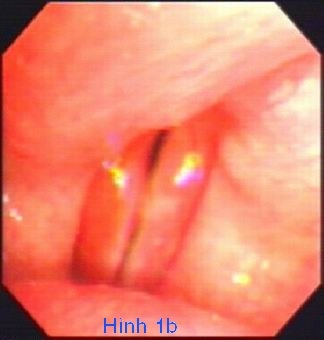

Việc chẩn đoán được thực hiện bằng cách kiểm tra trực tiếp các dây thanh âm bằng sợi quang (soi thanh quản).